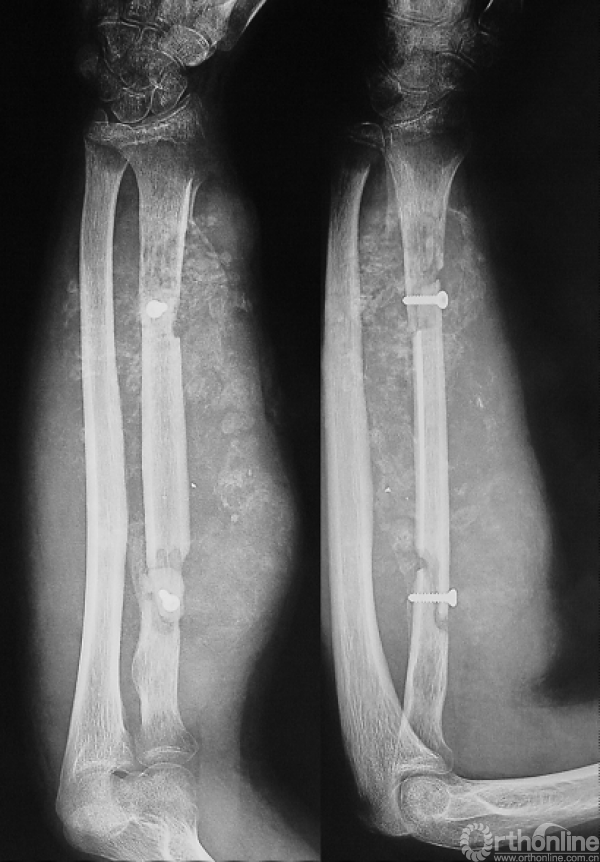

右上臂截肢术。

图14-11 第二次术后X线平片正位

肿瘤组织呈侵蚀性生长,瘤细胞呈宽条索状及团状结构,间富血窦及脉管,酷似血管肉瘤的组织形态,局灶性区域可见网状骨结构。诊断:骨肉瘤(血管扩张型)。

1.患肢局部皮肤条件不佳,影像学显示肿瘤巨大、与血管神经关系密切,且为术后复发,已无法评估血肿侵及范围,因此没有条件进行保肢治疗。术后的大体标本也证实了术前的判断。

2.即使已经出现肺转移,若局部不具备保肢条件,仍应行截肢手术,以降低局部复发风险。肺转移瘤的治疗应遵循外科手术与化疗相结合的原则。

3.在局部已无保肢条件的情况下,术前化疗已无必要,应先行外科治疗,再进行全身化疗。